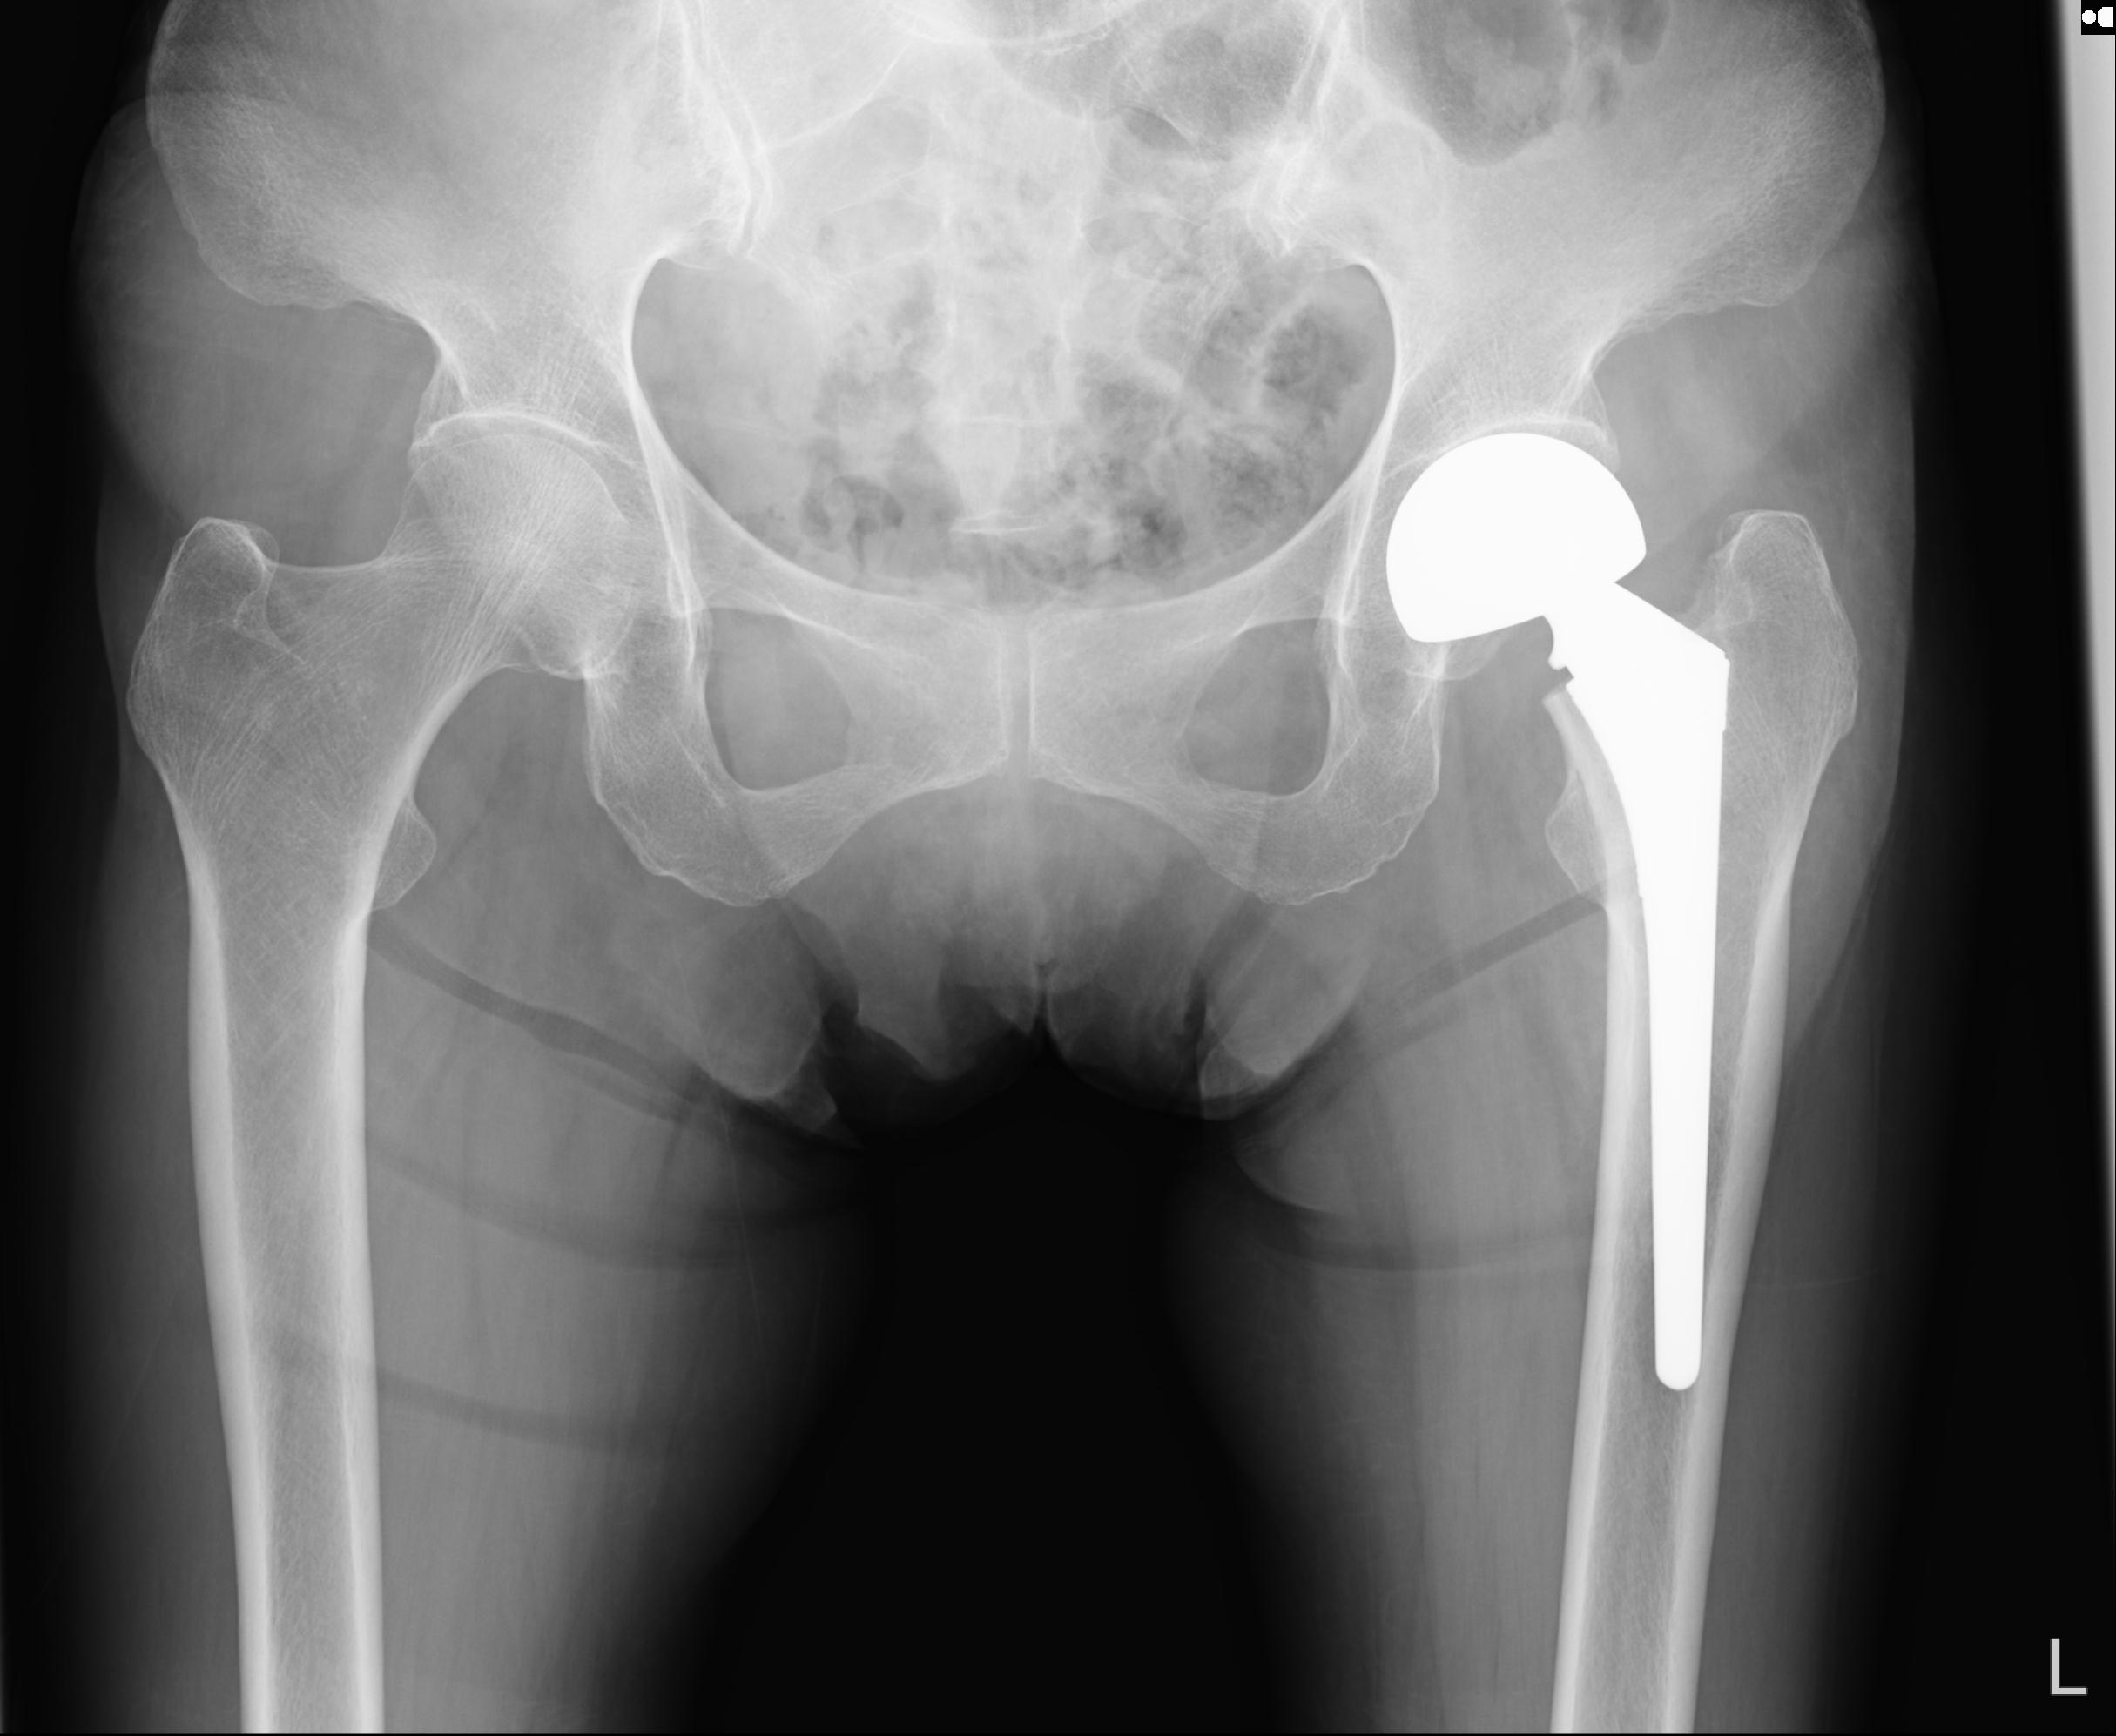

82084 1/14 1/20 股関節 2R 78歳男性 右人工骨頭